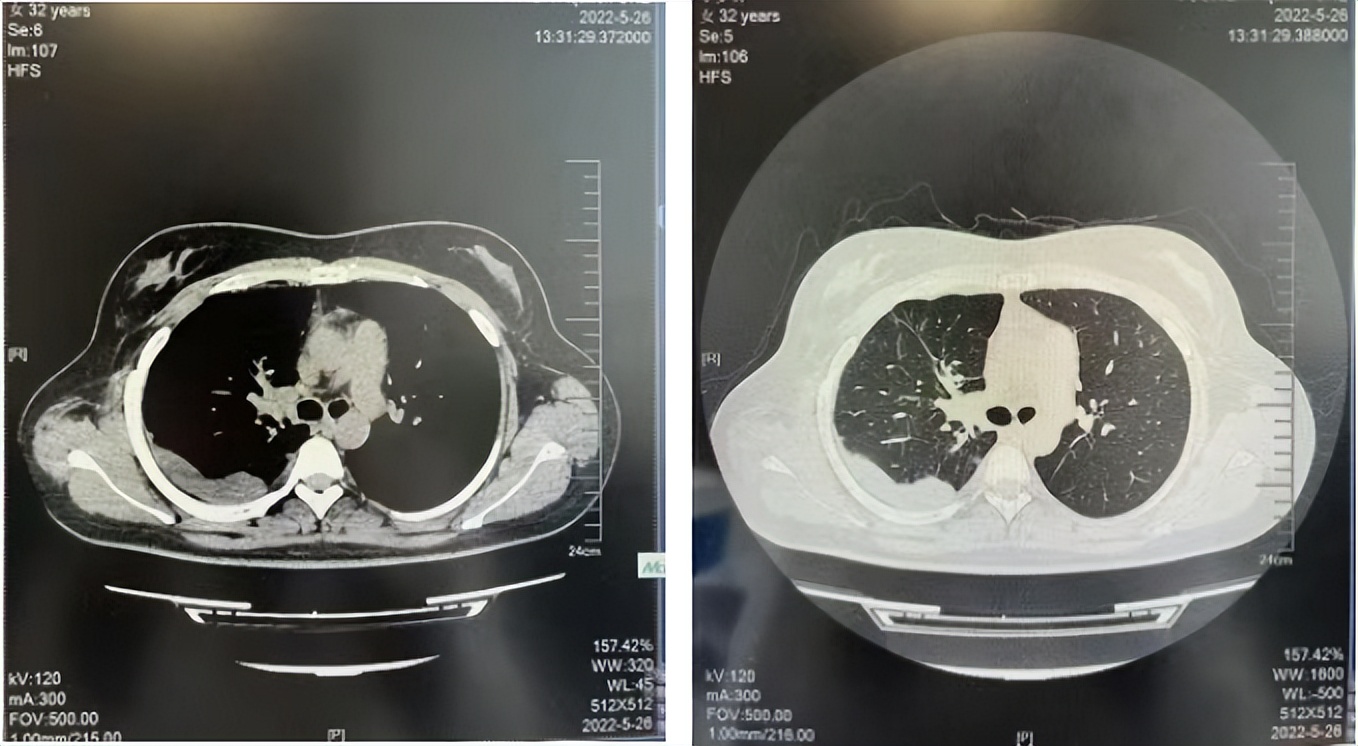

2016年1月复查CT提示支气管截断可见新发小结节,一线治疗采用培美曲塞+DDP方案化疗4周期(培美曲塞3.36,DDP 480mg)。化疗后复查胸部CT:右肺见不规则结节样影,最大层面大小约19mm*8mm,较前比较明显增大,疗效评估PD。2017.3-2017.4予单药多西他赛化疗3周期,疗效评估SD。2018年5月末复查CT提示结节较前增大,评效为PD,2018年6-10月予多西他赛+CBP化疗4周期,疗效评估SD。2022年5月患者出现活动后气短,复查胸部CT示右肺膨胀不良;右侧胸腔积液增多。胸腔积液包埋病理示符合肺腺癌细胞。行NGS基因检测:EML4:exon13-ALK:exon20融合。PD-L1(克隆号22C3)TPS<1%。

诊疗经过:2022年5月始口服克唑替尼3个月,出现肝功能异常(DILI 2级伴临床症状),改用恩沙替尼靶向治疗至今,目前评效为维持PR。恩沙替尼应用期间出现轻度肝功能异常(DILI 1级),对症处理后好转。截止目前PFS 33个月。

2018.07

2022.05

2022.08

2023.05